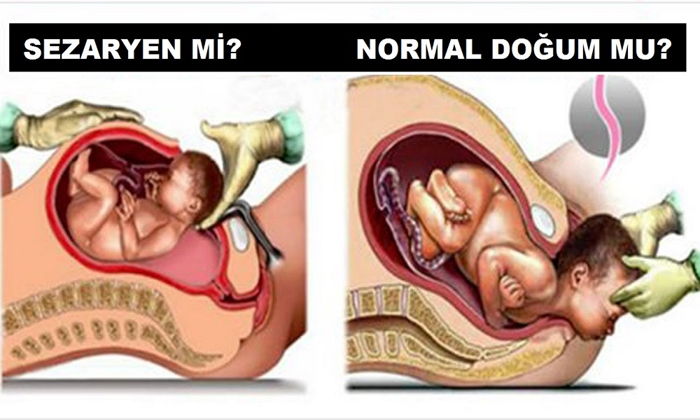

Anne istegiyle sezaryen

Normali normal dogum… Sezaryenin de hayat kurtarma operasyonu oldugunu hatirdan çikarmamak gerekli… Peki ya tibbi bir endikasyonu yani gerekçesi olmadan, sadece annenin istegiyle sezaryen olanlar? Bu konu sayfalarca tartisilabilecek bir konu.. Tartisiliyor da.. Bir de bu isin tibbi boyutu var.. Sonuçta, sezaryen de bir ameliyat ve avantajlari oldugu kadar dezavantajlari da var.

Ben bu yazida, anne istegiyle sezaryeni tibbi açidan ele alacagim.

Anne istegiyle sezaryen ne demektir?

Anne istegiyle sezaryen, annenin, vaginal dogum yapmamasini gerektiren tibbi ya da obstetrik endikasyonlarin yoklugunda, ilk dogumunu sezaryenle yapmasina verilen isimdir. Hastanin tibbi kararlarin verilmesine aktif olarak katilma hakkindan dolayi, son zamanlarda oldukça yayginlasmis bir uygulamadir.

Planlanmis sezaryenin olasi dezavantajlari

Hastanede yatma ve dogum sonrasi iyilesme süreçleri, sezaryenle dogumda vaginal doguma göre tipik olarak daha uzundur. Normal dogum yapan bir anne dogumdan sonra ayaga kalkip bebegiyle ilgilenebilecekken, sezaryen olan bir annenin bebegiyle birlikte kendisinin de birkaç gün bakima ihtiyaci olacaktir. Maternal morbidite de sezaryen dogumla daha yüksektir. Çalismalarda, postpartum kardiyak arrest, yara yeri hematomu, histerektomi, majör puerperal enfeksiyon, anestezi komplikasyonu gibi durumlarin riskleri sezaryen grubunda daha yüksek bulunmustur. Yenidoganin solunum sikintilari (respiratuvar distres sendromu, yenidoganin geçici tasipnesi) gibi durumlarin elektif sezaryen sonrasi vaginal doguma göre daha sik görüldügü bulunmustur, bu durumlar bebegin hastanede yatis süresini uzatabilir.

Anne istegiyle sezaryen olmayi planlayan hastalarin, ilerideki gebeliklerinde bebegin esinin asagida yerlesmesi (plasenta previa), bebegin esinin rashim duvarina gömülmesi (plasenta akreata), artmis rahim yirtilmasi riski, birden fazla karin ameliyati geçirmis olmaya bagli riskler (bagirsak hasari) gibi olumsuz durumlarin risklerinin artmis oldugunu göz önünde bulundurmasi gerekir.

Planlanmis sezaryenin olasi yararlari

Planlanmis sezaryenin tarihi siklikla önceden belirlenmistir. Bu, isle, evdeki diger çocugun bakimiyla ve annenin ihtiyaç duyabilecegi yardimla ilgili ayarlamalari yapabilmesine olanak verir. Planlanmis sezaryenler siklikla 39 – 40 haftalar arasinda gerçeklestirildiginden bebek günasiminin bebekle ilgili risklerinden korunmus olur. (Ancak hedef günasiminin risklerinden bebegi korumak ise, dogum indüksiyonunun da mantikli bir seçenek oldugu unutulmamalidir).

Planlanmis sezaryen durumunda dogum sonu kanamalar planlanmamis (acil) sezaryenlere ve vaginal dogumlara göre daha az görülür. Dogum sonu kanamalarin en sik nedeni uterin atoni (rahimin kendi kendini toplayip kanamayi durduramamasi) ve plasentanin parçalarinin rahim içinde kalmasidir ve planlanmis sezaryenle bu risk faktörleri en aza indirilebilir.

Planlanmis sezaryen, acil sezaryene göre birçok bakimdan daha az risk tasir. Bu risklerin arasinda, enfeksiyon, iç organlarda yaralanma, histerotomi esnasinda fetusun zarar görmesi, kanama ve anestezi komplikasyonlari sayilabilir.

Dogum sancilari baslamadan önce gerçeklestirilen sezaryen dogum, vaginal dogum sürecine bagli morbidite ve mortaliteyi (sakatlik ve ölüm), örnegin omuz takilmasi, sinir hasarlari, kemik travmalar, bebegin dogumda oksijensiz kalmasi gibi, azaltabilmektedir.

Perineal hasar ve üriner – fekal inkontinans gelisecegi korkusu, annelerin vaginal dogum yapmak yerine sezaryeni tercih etmesinin en önemli nedenlerindendir. Ancak bu endiseler bilimsel kanitlara ve çalismalara dayanmaz. Planlanmis sezaryen dogum sonrasi ilk aylarda idrar kaçirma orani daha düsük olsa da, bu oran iki – bes yil içinde vaginal dogum yapan hastalarda benzer olmaktadir. Ayrica, anne istegine bagli sezaryen dogum, uzun vadede üriner ve fekal inkontinanstan (idrar ve gayta kaçirma) koruyor gibi görünmemektedir.